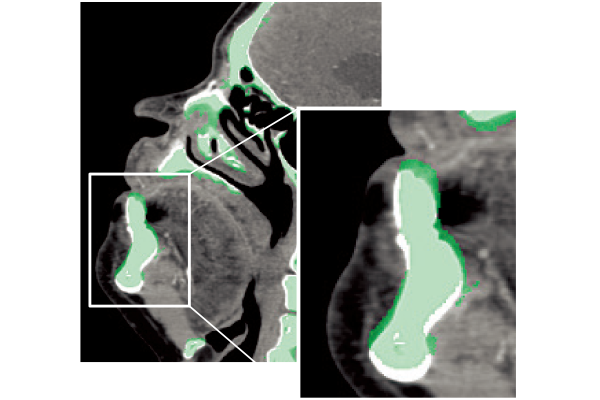

Non-rigid registration enables SYNAPSE 3D to match an organ in images acquired at different phases and different time points.

Rigid Registration

Non-rigid Registration